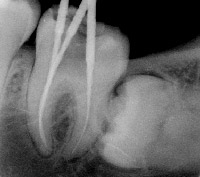

Перед проведением хирургической операции необходимо провести ревизию корневых каналов, на сколько это

возможно. Сделать рентгеновские снимки, и только потом планировать хирургическое вмешательство.

Резекция верхушки корня.

Наиболее часто применяемая операция при хронических очагах инфекции у верхушки корня зуба. Под анестезией

проводится отсечение верхушки коня зуба вместе с патологически измененными тканями. Эта методика

применяется в тех случаях, если корневой канал в силу своих анатомических особенностей пройти до

верхушки не получилось. Резекцию верхушки корня зуба проводят как на однокорневых, так и многокорневых

зубах.